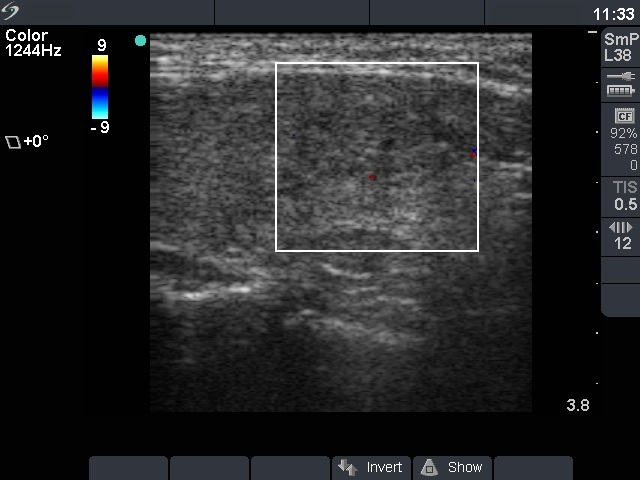

Benign nodular hyperplasia - Case 38. |

Ultrasonography: there was a small hypoechogenic lesion in the right and a moderately hypoechogenic nodule with microcalcifications in the left lobe. The vascularization was not specific.